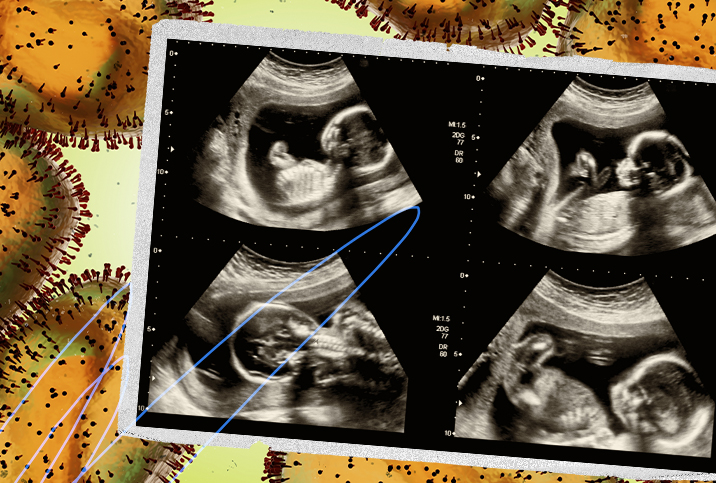

With virus cases on the rise, it's important expectant moms know how to keep themselves safe.